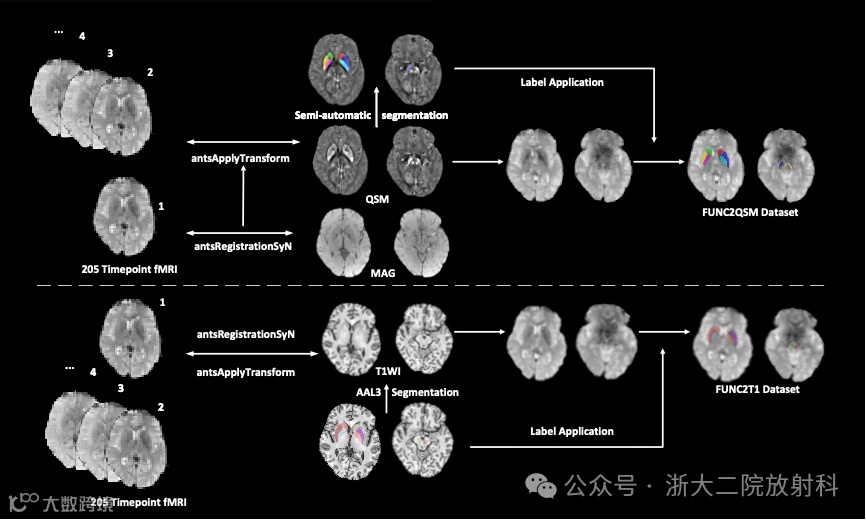

QSM引导精准功能连接分析框架助力帕金森病个体化诊断

PD是一种以基底节环路功能障碍为核心的神经退行性疾病。尽管静息态功能磁共振成像(rs-fMRI)在揭示PD患者的脑功能连接异常方面具有研究价值,但传统分析方法普遍依赖T1加权成像,在识别如黑质、红核、苍白球等深部脑结构时对比度不足,难以实现精准定位。该研究提出并验证了QSM引导下的精准功能连接分析框架,并在量化帕金森病中脑-基底节功能环路、个体化诊断帕金森病患者中取得了高鲁棒性和高准确性的效果,展示了QSM在功能神经影像领域的全新应用潜力,有望为克服静息态功能磁共振研究稳定性欠佳的缺陷提供潜在解决方案。